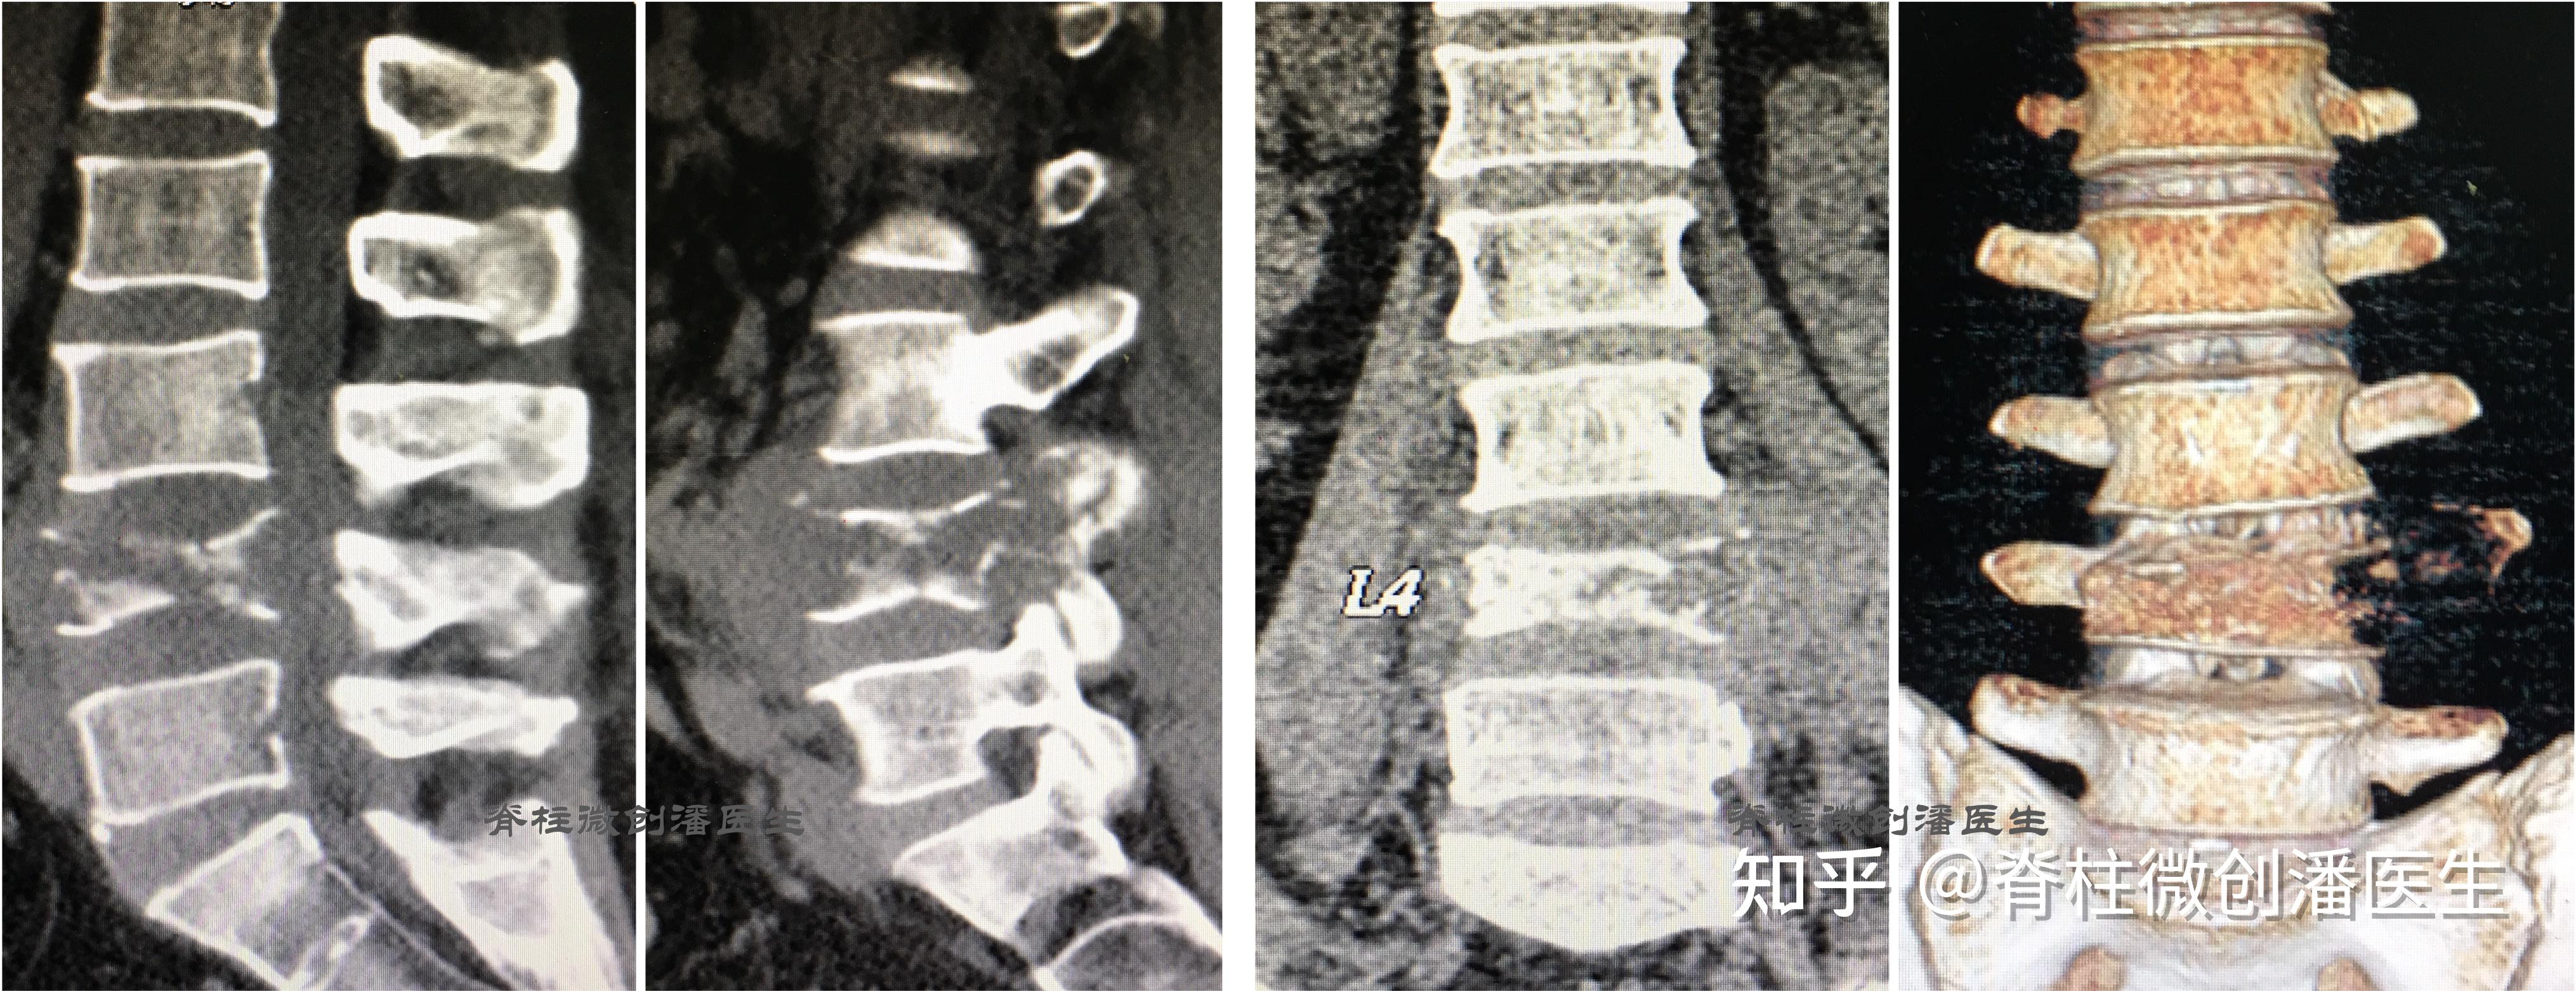

最常见的脊柱肿瘤脊柱转移瘤

图片尺寸4060x1562